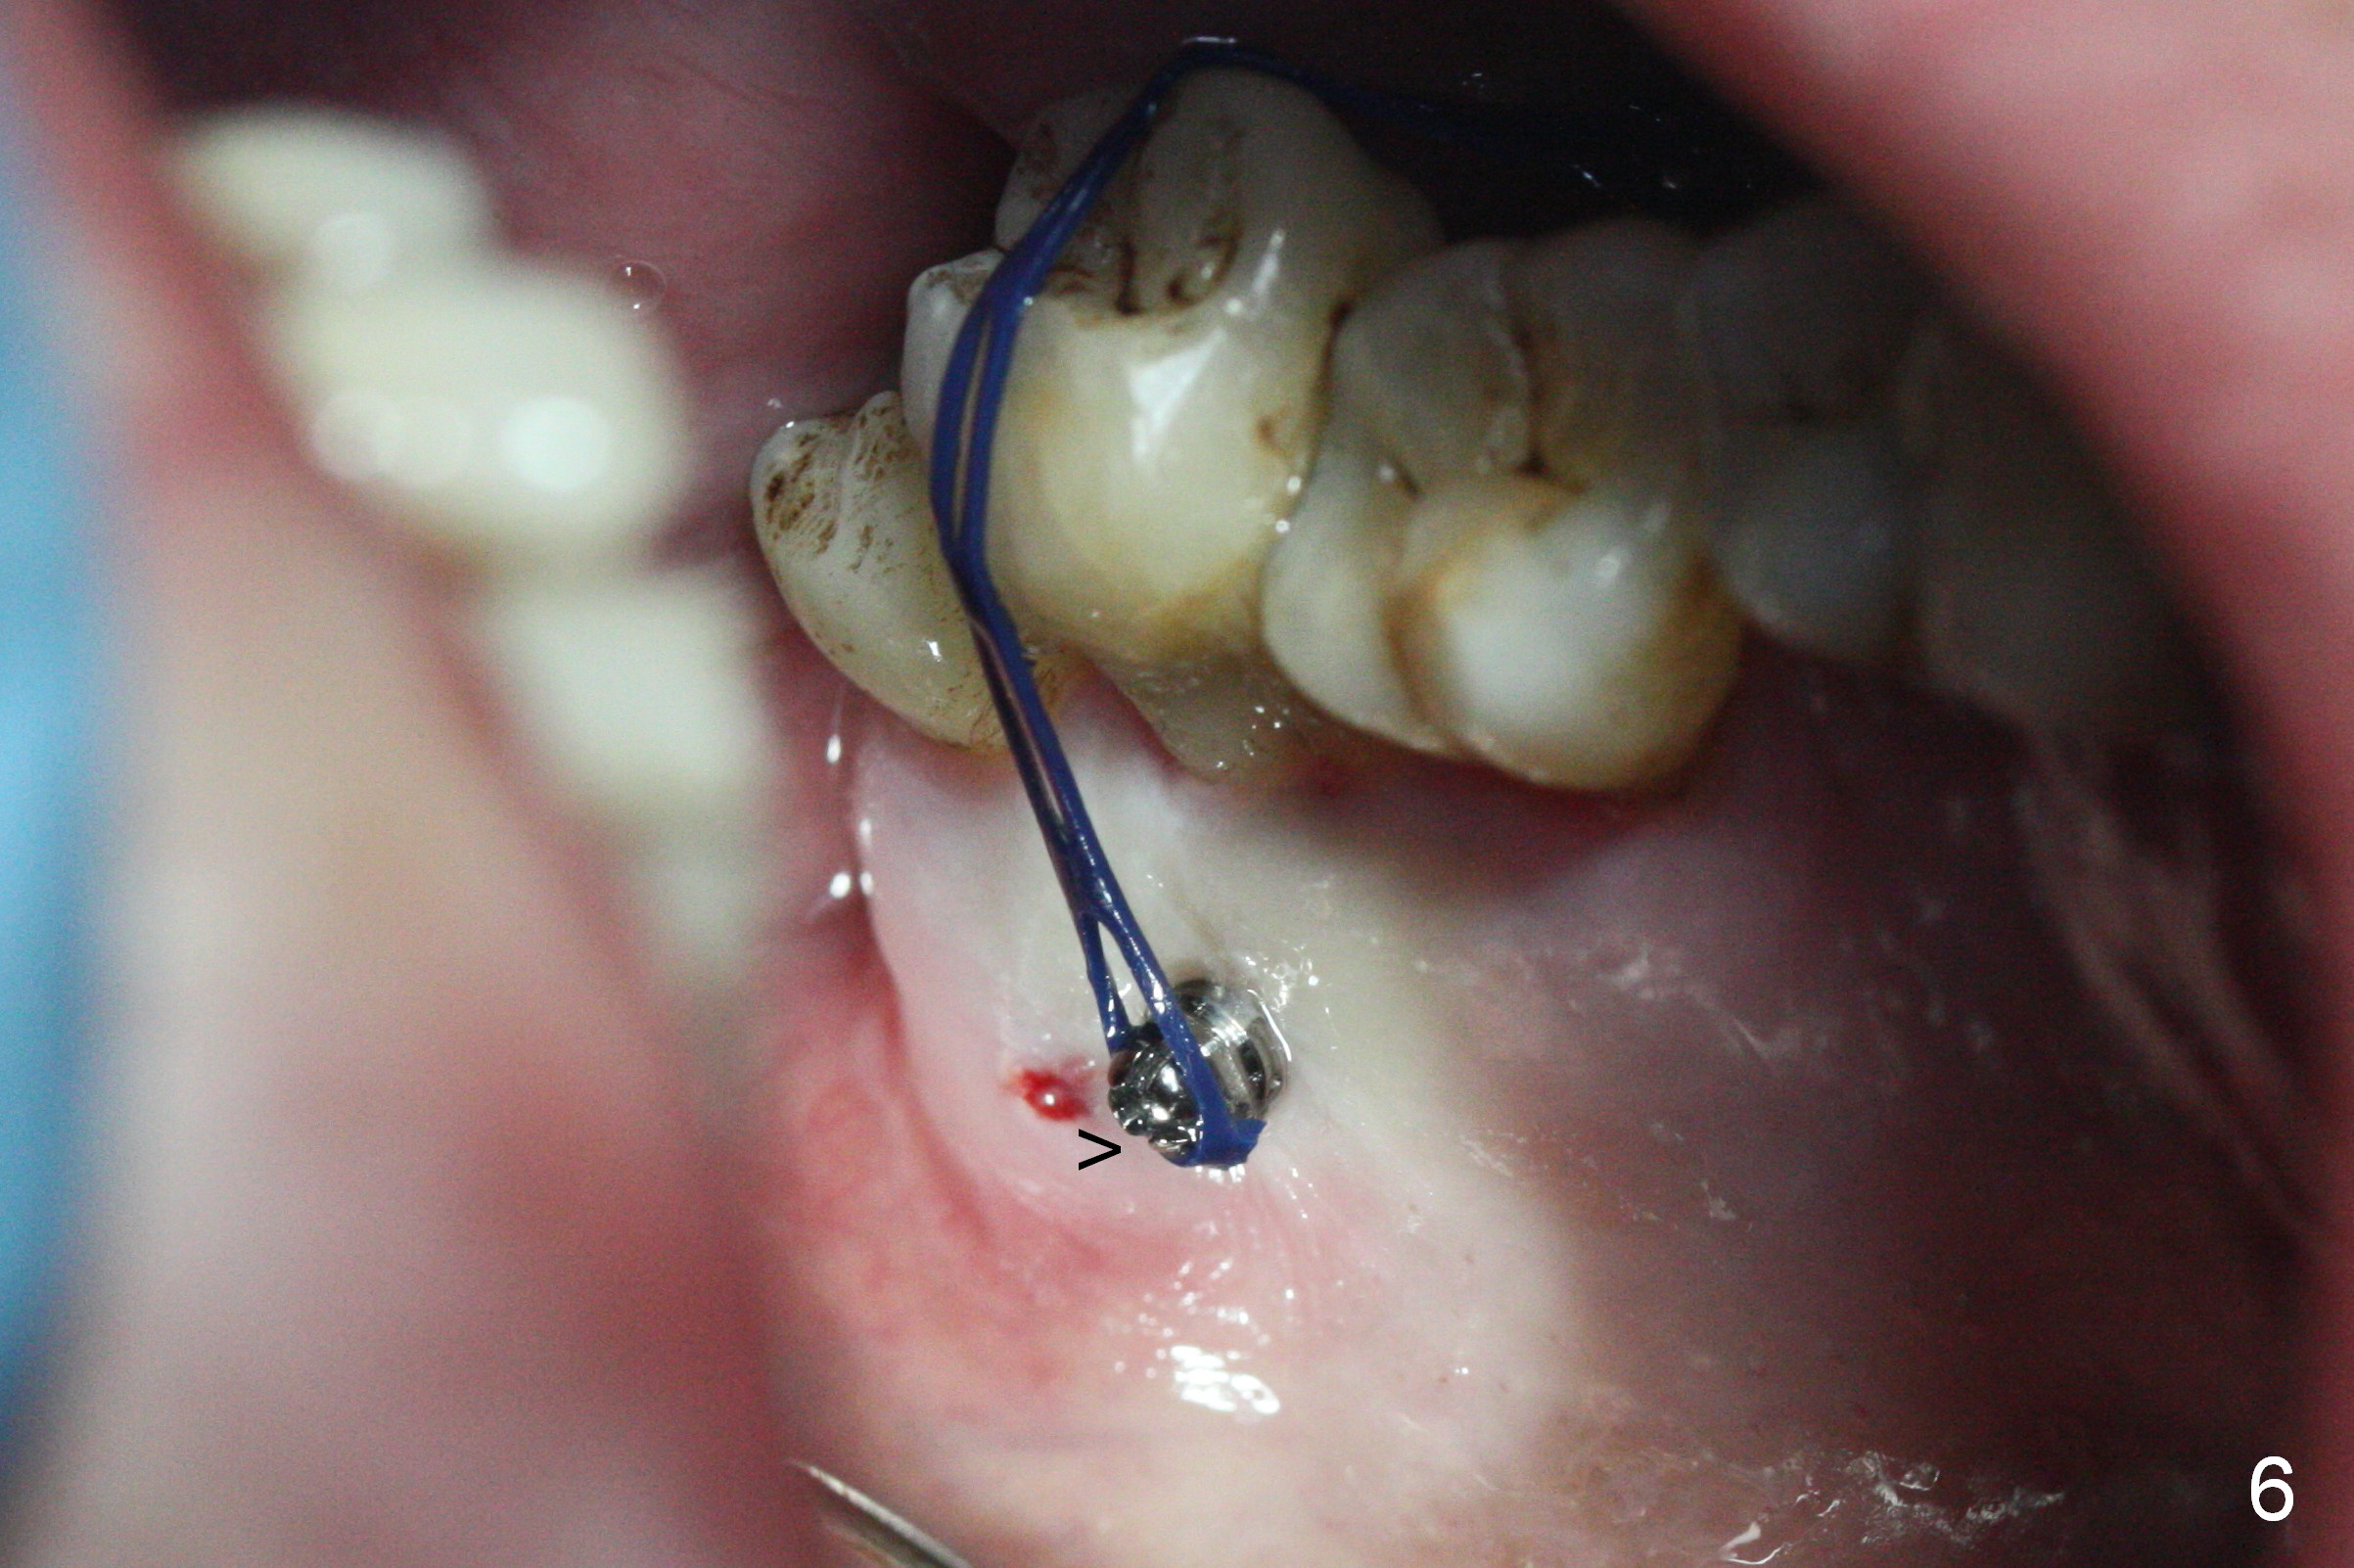

Two days post #31 implant placement, the patient returns for orthodontic intrusion of the tooth #2 with mini-implants (Fig.1). The palatal cusps have been trimmed (Fig.2 ^), since they almost contact a healing abutment at #31(*, Fig.3). Two mini-implants are to be placed mesiobuccal and distopalatal to the affected tooth. After minimal injection of Lidocaine, a 1.6x6 mm Tomas implant is placed in full length mesially (Fig.4), while the other (1.6x8 mm) half way (Fig.4). Following change in implant site mesially (Fig.6 >), the implant is half inserted (Fig.5). It appears that the tip of the distal implant is toward the tooth #1 (Fig.5). After withdrawing the implant partially, it is re-directed to apparently ideal trajectory (Fig.7). Ideally the mesial implant (Fig.8) should have been placed partially initially (Fig.4,5,7) so that the trajectory could have been able to be changed.